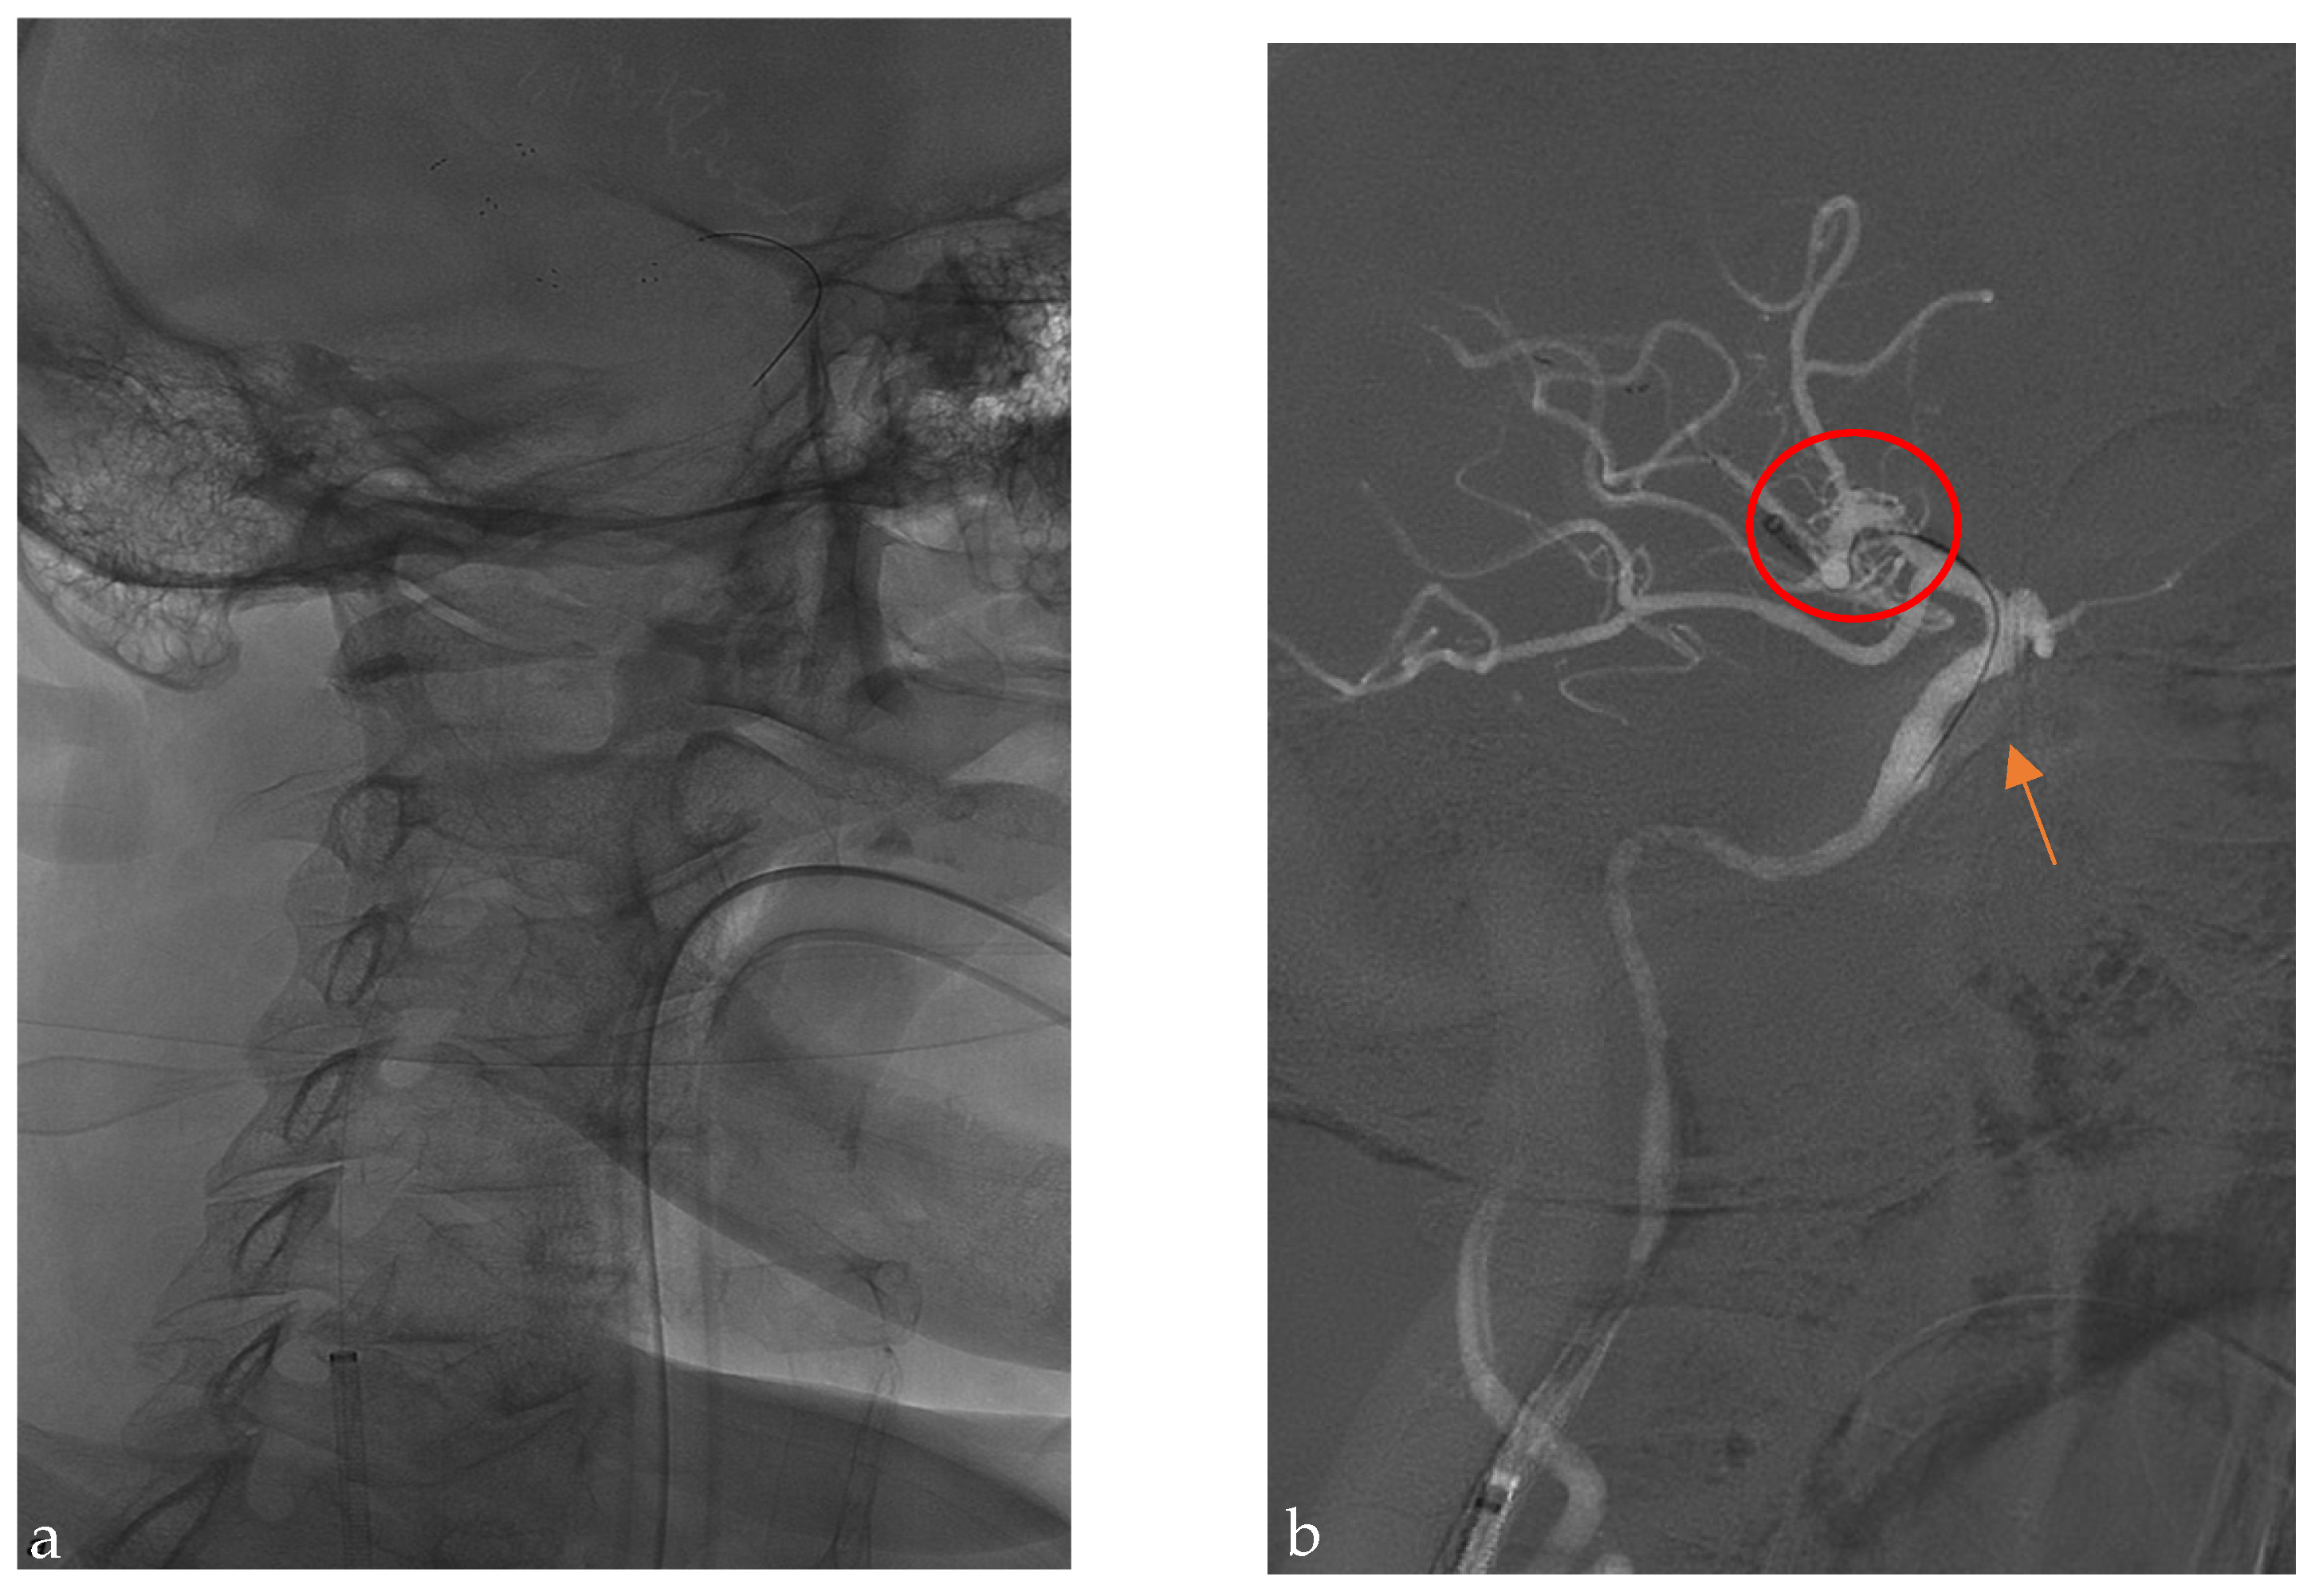

2.2. Endovascular Technique